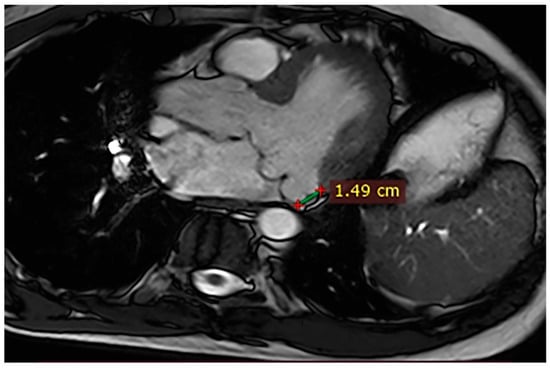

| 1 | Female, 61 years old | Syncope | 11 | MVP, mitral regurgitation | Lateral | Holter: atrial tachycardia and ventricular ectopy; cardiology follow-up planned for possible mitral valve repair |

| 2 | Male, 52 years old | Syncope and atypical chest pain | 10 | - | Lateral | History of ventricular arrhythmias; cardiology follow-up and Holter monitoring recommended |

| 3 | Female, 74 years old | Extrasystole | 3 | - | No LGE | No LGE; patient reassured and scheduled for periodic clinical follow-up |

| 4 | Male, 34 years old | Extrasystole in Marfan syndrome | 15 | MVP, valvular regurgitation | No LGE | Marfan syndrome; MVP with regurgitation; regular cardiology follow-up advised. |

| 5 | Male, 63 years old | Heart failure | 2,5 | MVP, valvular regurgitation | No LGE | Reduced LVEF (47%) with left atrial dilatation; heart failure therapy optimized; follow-up planned. |

| 6 | Male, 68 years old | Palpitations | 5 | - | Lateral | LGE in basal lateral wall; electrophysiological evaluation and ECG monitoring recommended. |

| 7 | Female, 53 years old | Extrasystole and syncope | 15 | MVP, valvular regurgitation | Basal-lateral | Extensive MAD with MVP and LGE; increased arrhythmic risk; antiarrhythmic therapy considered. |

| 8 | Female, 63 years old | Aortic and mitral regurgitation | 11 | Aortic and mitral regurgitation | Lateral | Aorto-mitral regurgitation with septal hypokinesia; mitral valve repair performed; heart failure therapy started. |

| 9 | Male, 45 years old | Palpitations and vertigo | 10 | - | Lateral | Basal lateral LGE; regular clinical and ECG follow-up recommended |